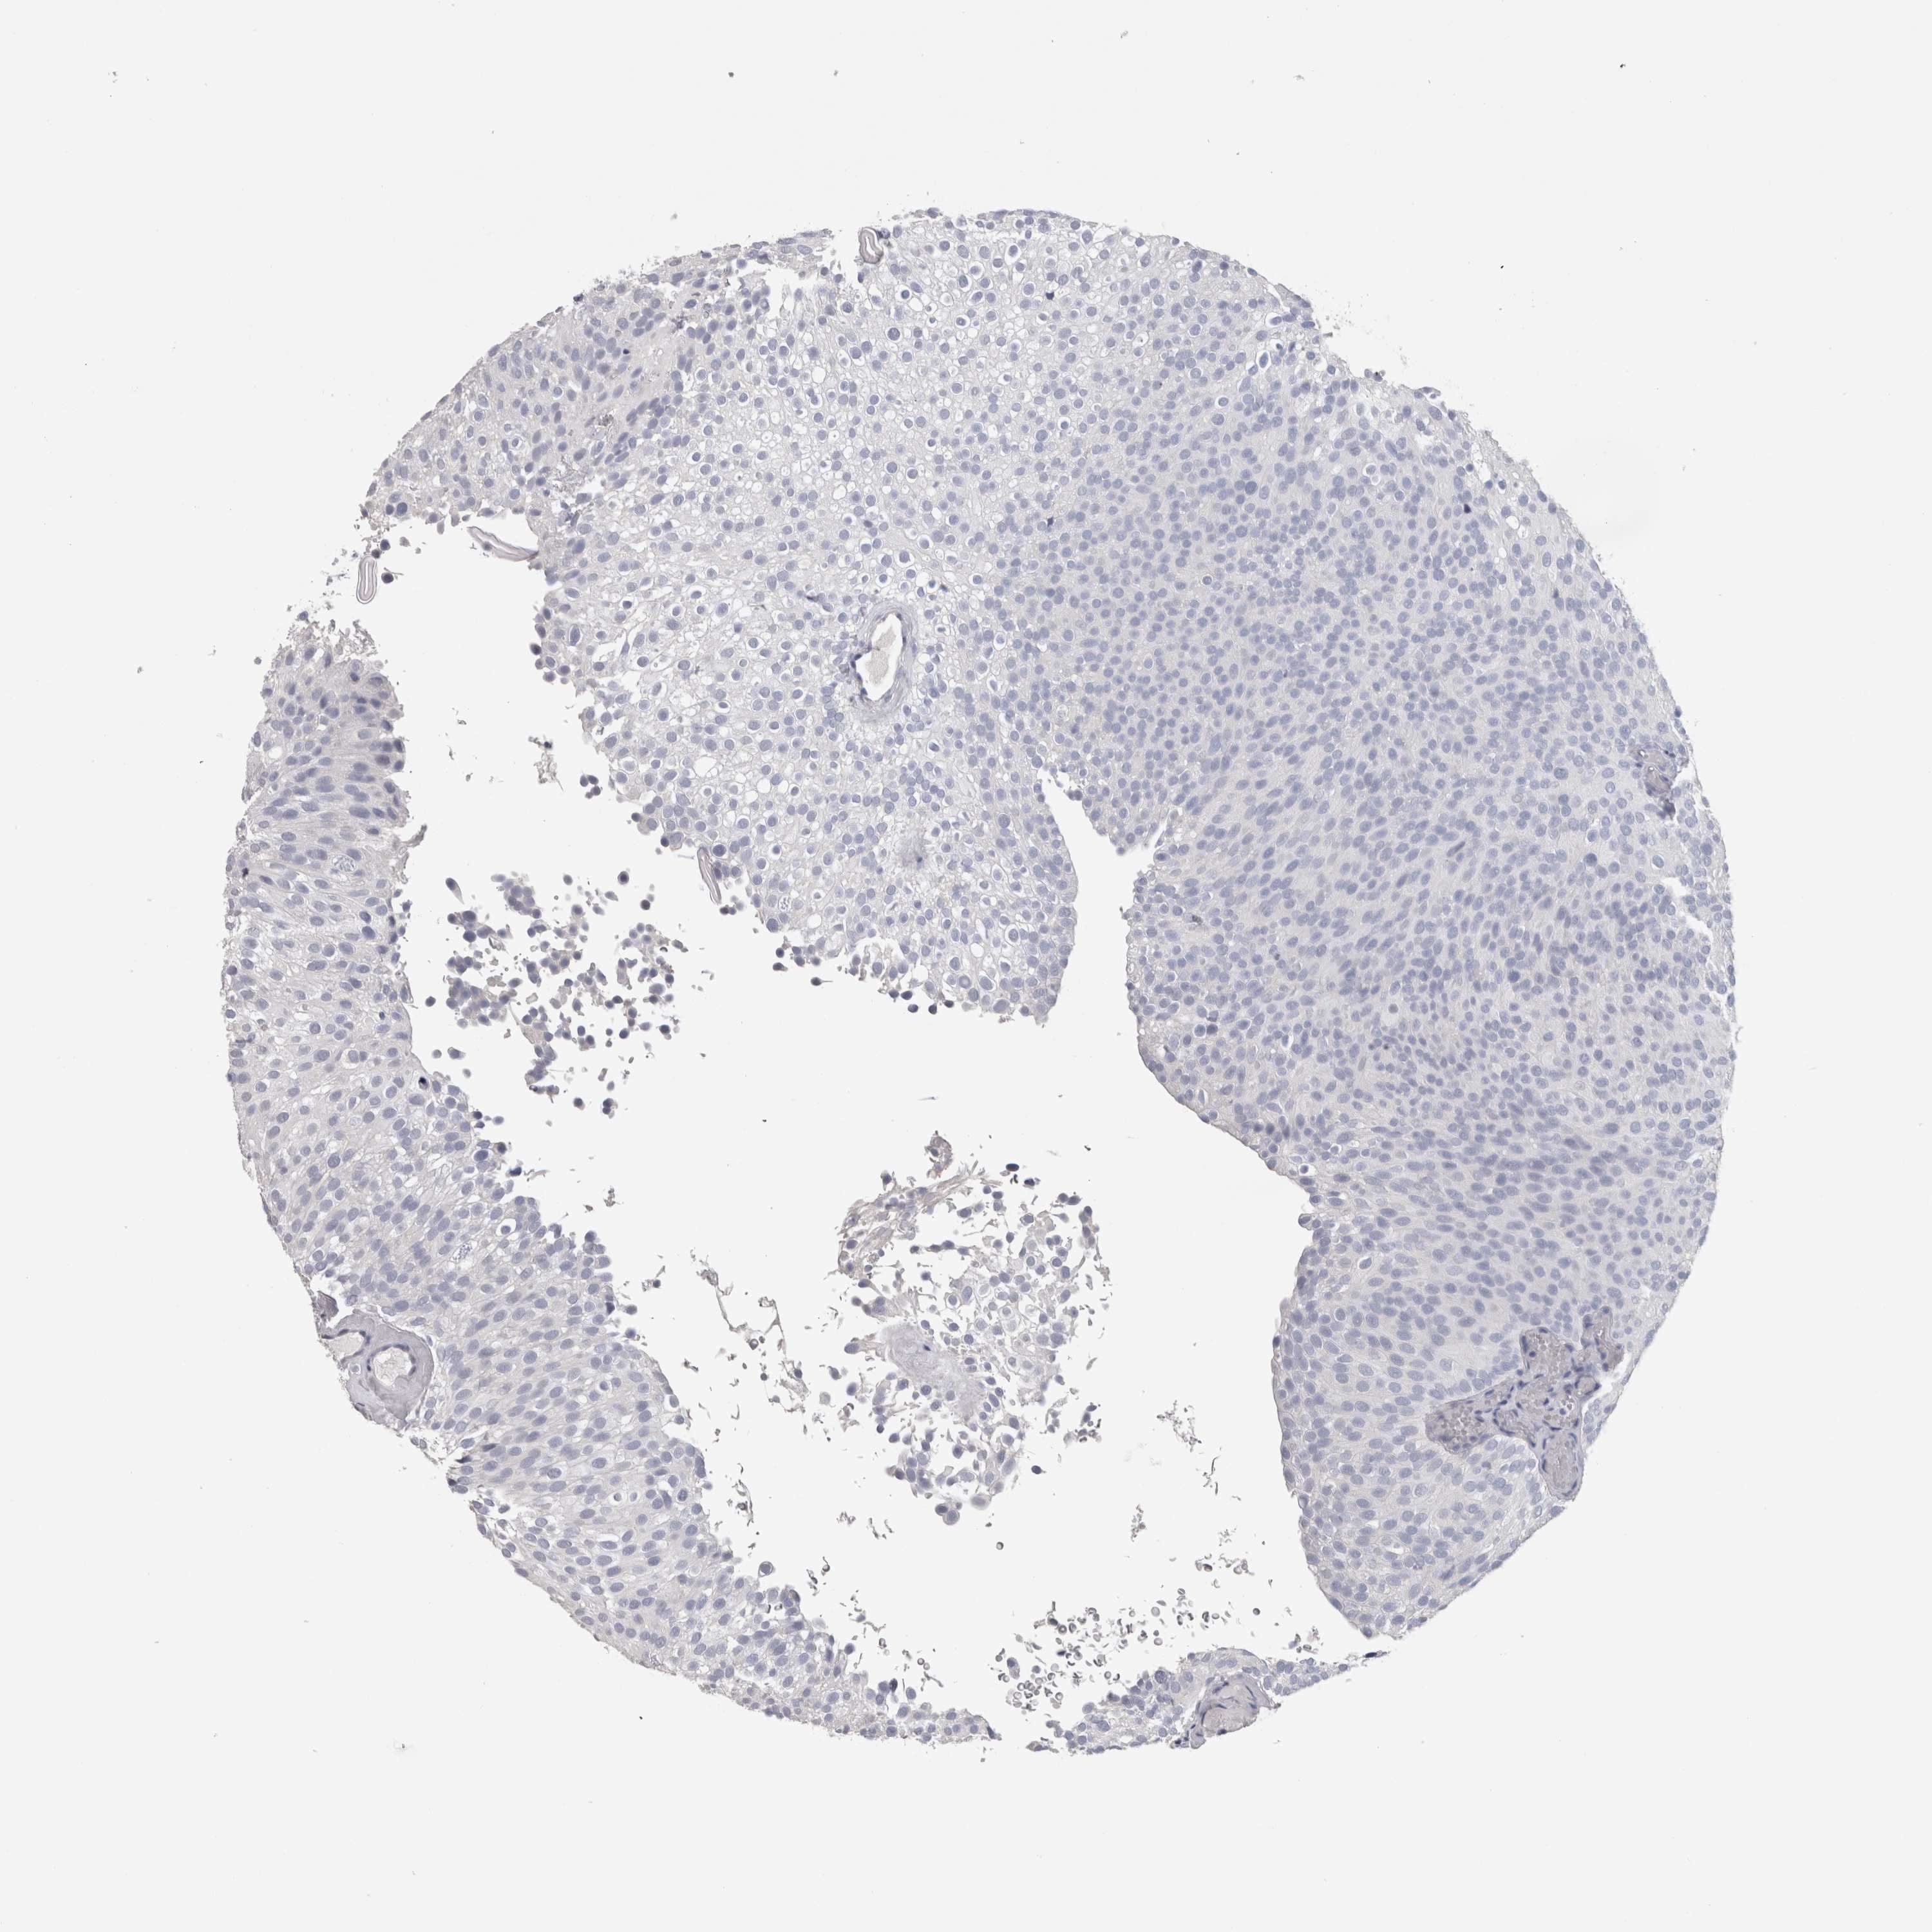

UROTHELIAL CANCER - Protein expressioni

A mouse-over function shows sample information and annotation data. Click on an image to view it in a full screen mode. Samples can be filtered based on level of antibody staining by selecting one or several of the following categories: high, medium, low and not detected. The assay and annotation is described here.

Note that samples used for immunohistochemistry by the Human Protein Atlas do not correspond to samples in the TCGA dataset.

Antibody stainingi

Antibody staining in the annotated cell types in the current human tissue is reported as not detected, low, medium, or high, based on conventional immunohistochemistry profiling in selected tissues. This score is based on the combination of the staining intensity and fraction of stained cells.

Each image is clickable and will lead to virtual microscopy that enables deeper exploration of all samples and also displays staining intensity scores, fraction scores and subcellular localization as well as patient and tissue information for each sample.

Antibody HPA024748

Antibody CAB025545

Antibody CAB047309

Urothelial carcinoma, Low grade

Urothelial carcinoma, High grade

Urothelial carcinoma, NOS